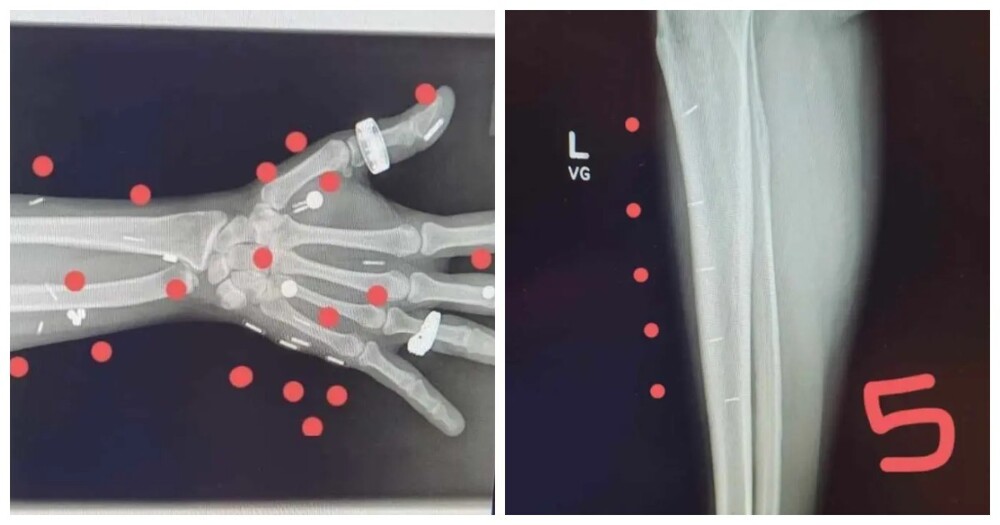

Синн, что называется, вошла во вкус и стала обладательницей 52 имплантов, половина из которых – это чипы. Для того чтобы зафиксировать рекорд, ей пришлось сделать рентгеновский снимок и на практике показать, для чего нужна та или иная модификация.